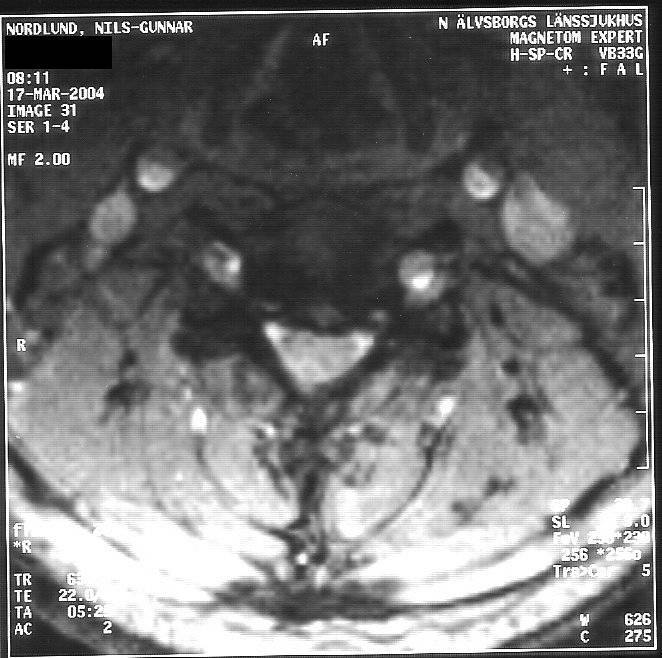

Jag bifogar även ett antal, av mig digitaliserade bilder från MR, 2004-03-17;

Bild 31